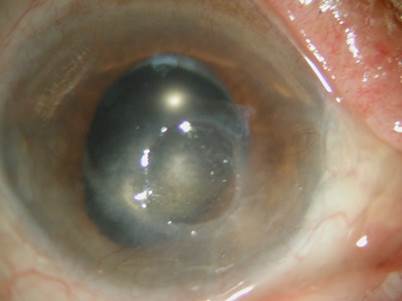

각막상피각막염은 실제 바이러스가 활성화되서 살아있는 상태로 소수포-> 가지모양 궤양(사진) -> 지도모양궤양(사진) -> 흉터 순으로 진행이되며 통증과 눈부심, 눈물, 시력감소와 같은 증상이 발생합니다. 또한 각막의 감각도 소실되거나 줄어들어 궤양정도에 비해서는 세균각막염보다 통증은 덜할수 있습니다. 치료는 감염상피를 제거하고 항바이러스제 안약을 점안해야하며 2-3주간 점안해야합니다. 스테로이드는 바이러스 활성을 증가시킬 수 있기 때문에 감염상피각막염에서는 사용하지 않는게 좋습니다.